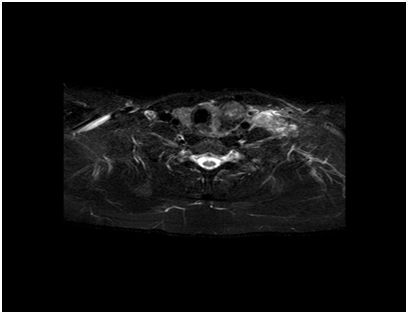

Cross sectional imaging modalities are not indicated in the vast majority of thyroid nodules. CT scan are usually considered in patients with suspected tracheal compression, retro-sternal extension and lung metastasis in cases of malignant nodules. A full body CT scan is indicated in patients with primary or secondary lymphoma of thyroid to stage the disease (Figure 2-4). MRI scans are indicated in cases of thyroid nodules presenting with palpable lateral compartment neck nodes.

Figure 3 CT Coronal view - tracheal compression.

Figure 4 MRI showing left thyroid nodule with lateral neck nodes in papillary cancer.